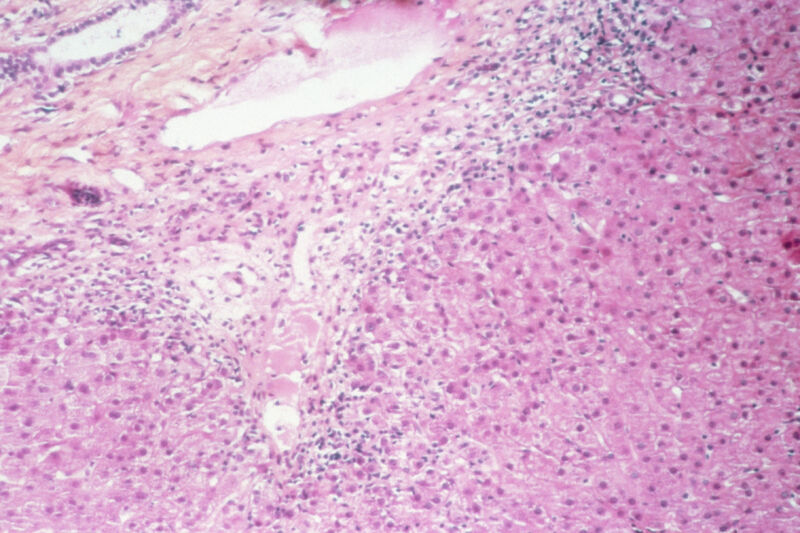

Liver lesions in patient with chronic active hepatitis C.

Enlarge / Liver lesions in patient with chronic active hepatitis C. (credit: Getty | BSIP)